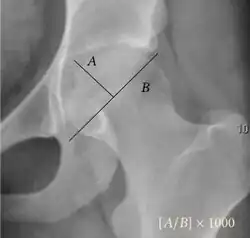

Acetabular depth ratio | ![]() |

Deepness of acetabulum. | >250

|